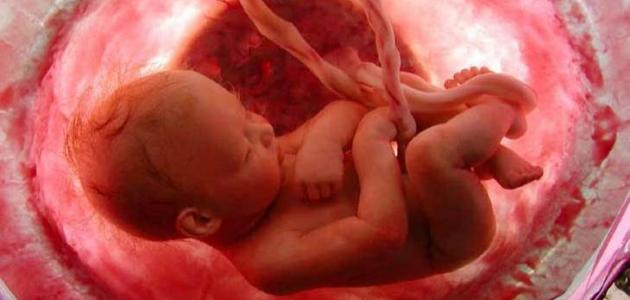

تُعَدُّ المشيمة (بالإنجليزيّة:Placenta) واحدة من أهمِّ الأشياء التي تنمو داخل الرحم خلال فترة الحمل، حيث إنّها تنمو وتكبر داخل الرحم كما الجنين، إلا أنَّها تتَّخذ شكل الفطيرة، وعادةً ما يبلغ قطرها عند الولادة حوالي 22 سم، ويصل سمكها من المنتصف إلى حوالي 2.5 سم، وتُعتبَر المشيمة نقطة التواصل بين الأم وجنينها؛ حيث ينقل دم الأم الأكسجين والعناصر الغذائيّة المهمَّة لنمو الجنين إلى المشيمة، لينقلها الحبل السرِّي من الجانب الآخر إلى الجنين، وعلى الرغم من تناقل المواد عبر الدم بين الأم وجنينها من خلال المشيمة أثناء الحمل؛ إلا أنَّ دمهما لا يختلط، بل تحافظ المشيمة على دم الجنين مفصولاً عن دم الأم.[١]